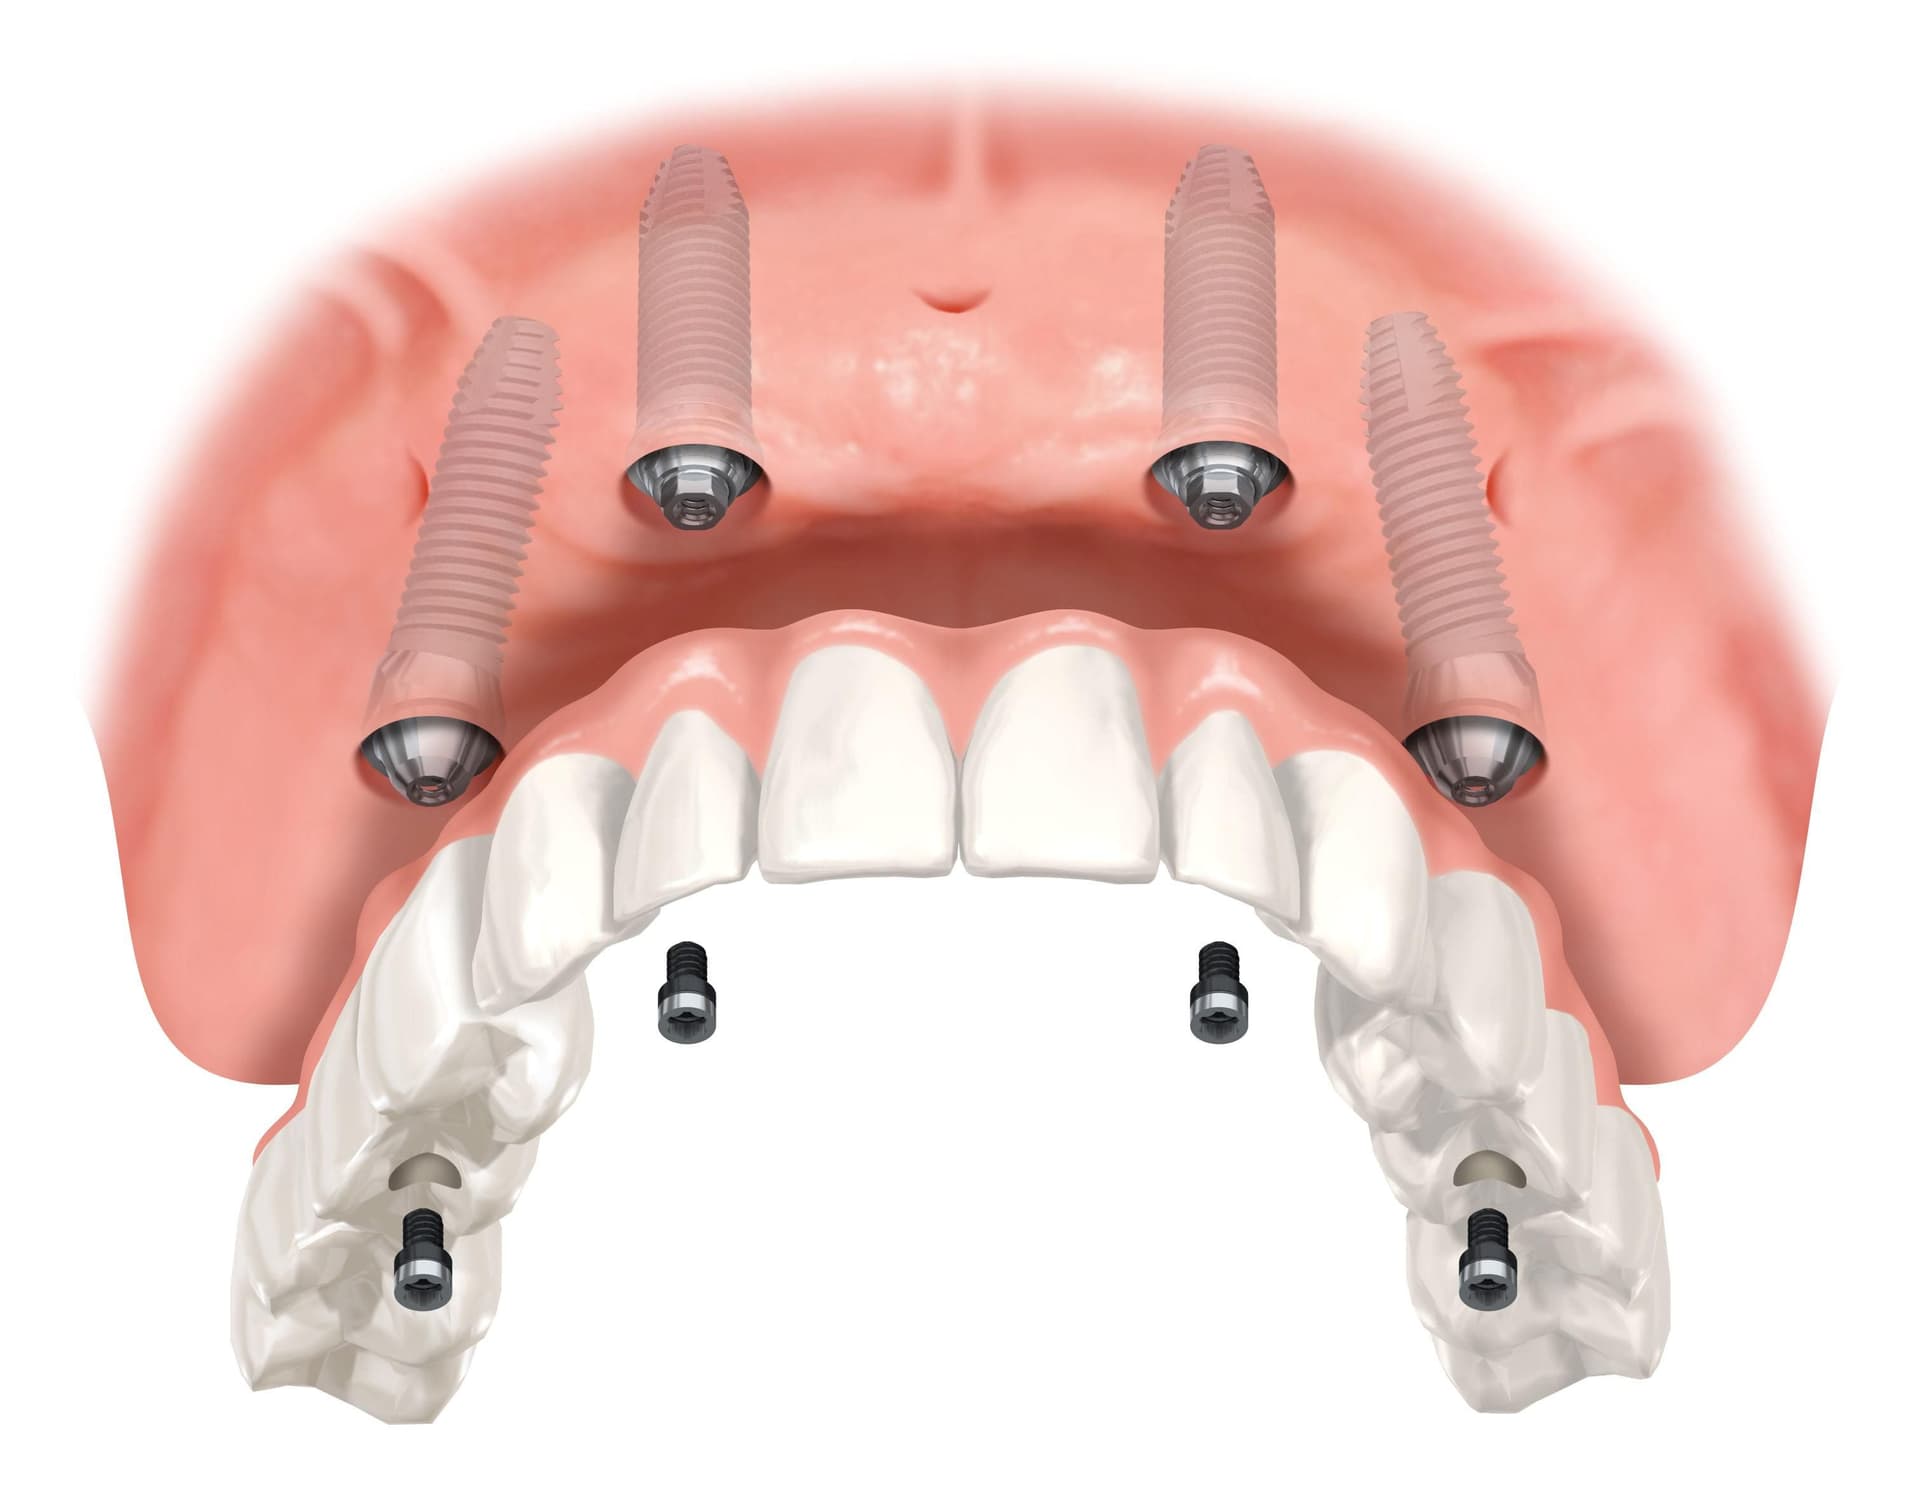

Hvis du skal erstatte en hel kjeve med implantater